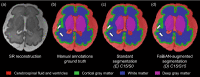

Accurate characterization of in utero human brain maturation is critical as it involves complex and interconnected structural and functional processes that may influence health later in life. Magnetic resonance imaging is a powerful tool to investigate equivocal neurological patterns during fetal development. However, the number of acquisitions of satisfactory quality available in this cohort of sensitive subjects remains scarce, thus hindering the validation of advanced image processing techniques. Numerical phantoms can mitigate these limitations by providing a controlled environment with a known ground truth. In this work, we present FaBiAN, an open-source Fetal Brain magnetic resonance Acquisition Numerical phantom that simulates clinical T2-weighted fast spin echo sequences of the fetal brain. This unique tool is based on a general, flexible and realistic setup that includes stochastic fetal movements, thus providing images of the fetal brain throughout maturation comparable to clinical acquisitions. We demonstrate its value to evaluate the robustness and optimize the accuracy of an algorithm for super-resolution fetal brain magnetic resonance imaging from simulated motion-corrupted 2D low-resolution series compared to a synthetic high-resolution reference volume. We also show that the images generated can complement clinical datasets to support data-intensive deep learning methods for fetal brain tissue segmentation.